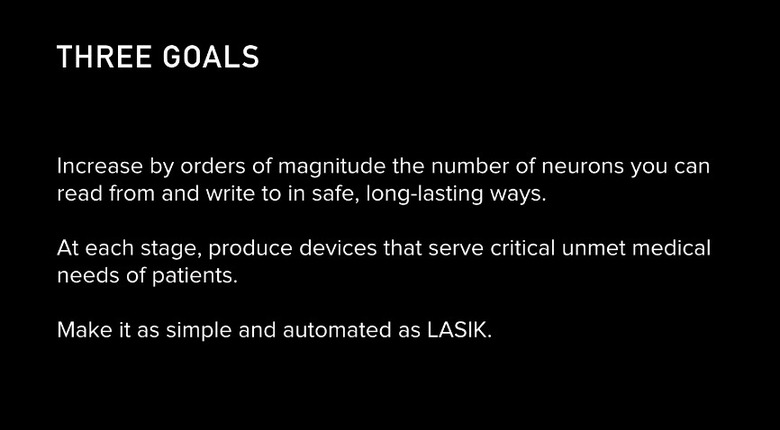

The results so far come from testing on lab rats implanted with as many as 1,500 electrodes, which, everyone should be warned, may or may not transfer smoothly to work on humans. If it does work, Neuralink says its intention for the technology at first is to do things like help amputees, or restore the ability to see, talk and listen. Of course, as Elon has said previously, he believes that connecting our brains to computers will eventually be the only way to keep up with the progression of artificial intelligence, so while things may start here the plan is for something much more powerful.

According to the article, its bundles of flexible threads are about one quarter the diameter of a human hair, implanted using needles to avoid blood vessels on the brain's surface. Then the embedded sensors capture information and send it to a receiver (the chip above) on the surface of the skull. From there it transmits wirelessly — Elon Musk said it could Bluetooth the information to your skull. Right now implantation requires drilling holes, but researchers hope in the future they can use lasers to avoid "unpleasant" vibration.

Neuralink president Max Hodak went on to explain why it's embedding sensors directly into the brain, near but not in neurons. Simply, it's the only way to send and receive the information necessary, from "spikes" of activity. A neurosurgeon is also part of the presentation, showing off some videos of the implantation technology, and how its robot can install thousands of wires directly into the brain while avoiding tissue damage and bleeding. Eventually, they'd like to do it without shaving the patient's head, although he acknowledged that the first operations will be more like current deep brain implants.